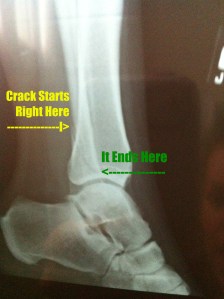

I ended up breaking the fibula straight across, with another slight crack above it. You’ll see on the x-ray that only the top of the crack displaced so we didn’t need to put a pin in…thank goodness. Once we got to the ortho and he reviewed the films, he found another fissure crack on the inner ankle bone. After being wrapped up, the Ortho decides on a walking boot. I am so glad for many reasons, but the obvious were that 1. I could shower and 2. My foot swelled so bad (I swear it was the size of a football) that I kept having to loosen it. A hard cast wouldn’t have allowed that.